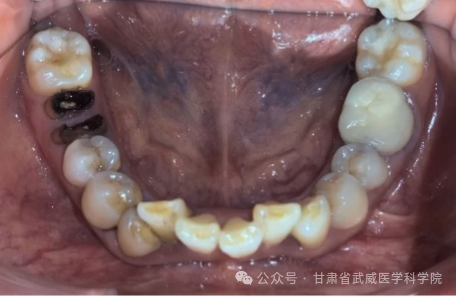

牙列不齐,医学上称为“错颌畸形”,是指儿童在生长发育过程中,由先天的遗传因素或后天的环境因素(如疾病、口腔不良习惯、替牙异常等)导致的牙齿、颌骨、颅面的畸形。

·清洁死角多: 牙齿重叠交错,容易藏匿食物残渣和牙菌斑,刷牙刷不干净。

·引发牙病: 极易导致龋齿(蛀牙)、牙龈炎、牙周病(牙龈红肿、出血、萎缩)。

·异常磨损: 牙齿排列不齐会导致咬合力量分布不均,个别牙齿过度磨损,出现酸痛、敏感甚至断裂。

·替牙障碍: 乳牙过早脱落或迟迟不掉(滞留),导致恒牙萌出位置不够或错位。